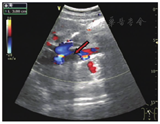

患者2女性,53岁。因"腹部持续性隐痛,阵发性加重,偶有腰背部疼痛,发热2 d"于2018年11月16日入院。入院当天行彩色多普勒超声检查发现下腔静脉近段血流充盈缺损,管腔内可见一规则、边缘整齐、高回声的实质性、漂浮条索状物,狭窄率为60%~70%,长约6.0 cm,上缘距右心房约3.0 cm。右肾静脉内无血流显示(图5)。由于此漂浮物较长,距右心房距离较近,无法行下腔静脉滤器置入术,于2018年11月26日全麻下行右肾切除术+下腔静脉瘤栓切除术,术中剖腹探查发现右肾静脉内无血流充盈,可扪及实性质韧肿物由肾实质内延伸至下腔静脉内,沿右肾静脉根部剖开下腔静脉壁,见静脉内黄色光滑质韧瘤栓,呈漂浮样与静脉无粘连,予以取出(图6)。术后患者生命体征平稳。术后病理诊断:右肾血管平滑肌脂肪瘤。患者术后行彩色多普勒超声检查,提示下腔静脉内管壁光滑,管腔内径正常,血流通畅,充盈良好(图7)。患者于2018年12月5日出院。